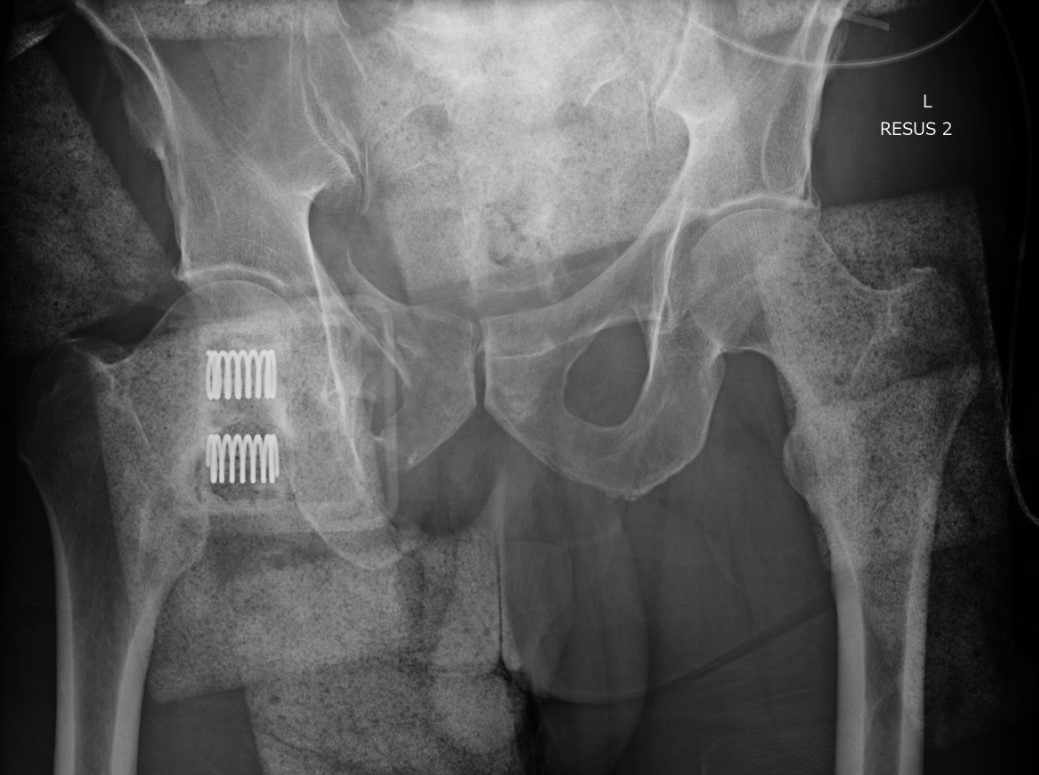

APC pre binderAPC post binder

APC fracture pre- and post binder (note improper position cranial to trochanters)